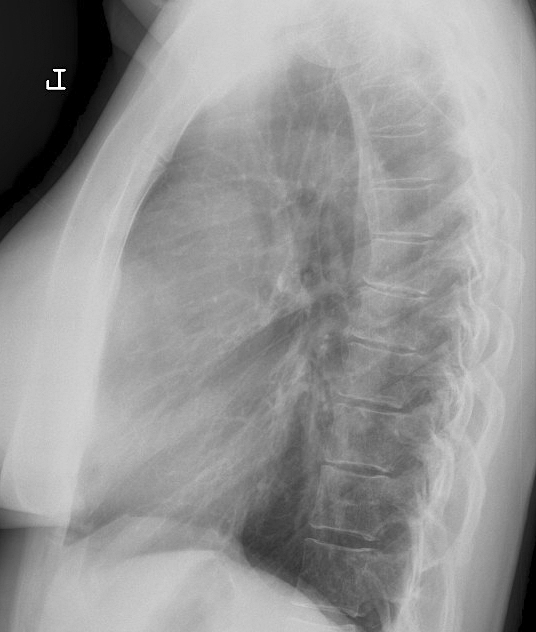

Thymoma